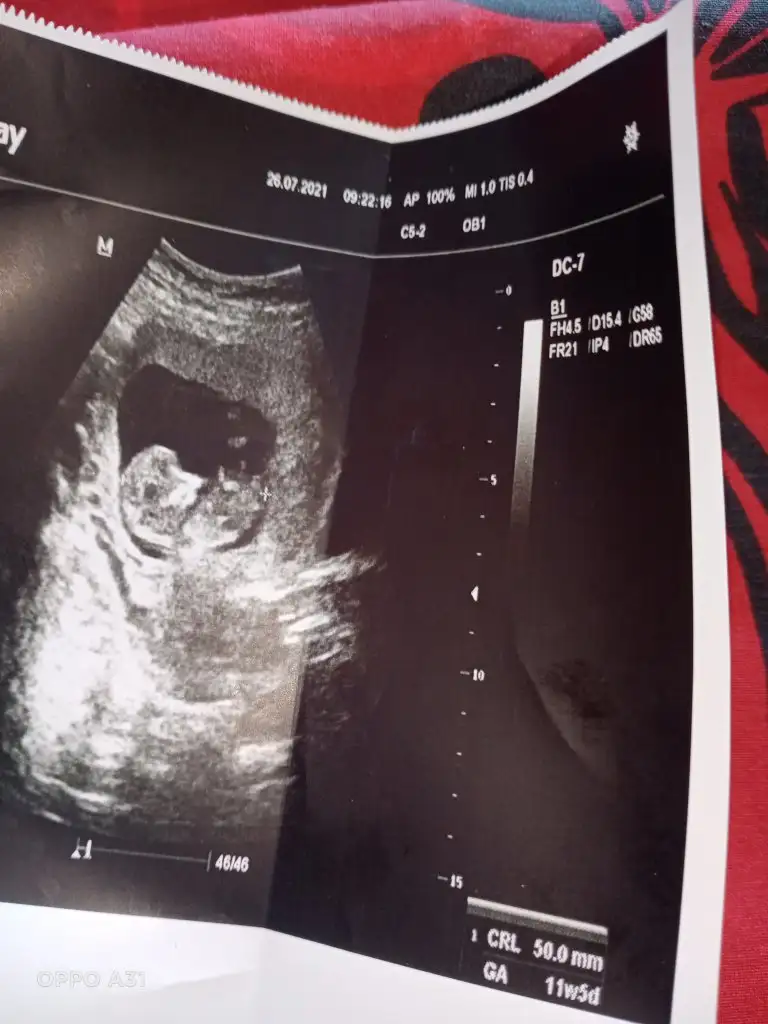

Kız gibi sanki emin olamadımEki Görüntüle 2892053 Eki Görüntüle 2892054 @Ikra meyra acaba müsait olunca bakar mısın? 11+6 oldu belli olur mu biraz?

Benim bebeğime de bakar mısınız 9 buçuk haftalık. Belki erken ama bir yorumunuz olursa diye merak ediyorumEn iyi 11 12 13 haftalar olmalışimdilik erkek yönünde ama yanıltabilir dediğim haftalar olmalı

Erkek görünüyor

Şimdilik erkek yönünde ama en iyi 11 12 13 haftalar olmalı tekrar USG paylasinBenim bebeğime de bakar mısınız 9 buçuk haftalık. Belki erken ama bir yorumunuz olursa diye merak ediyorum

6haftalik 10 ve 11haftalik görüntüsü